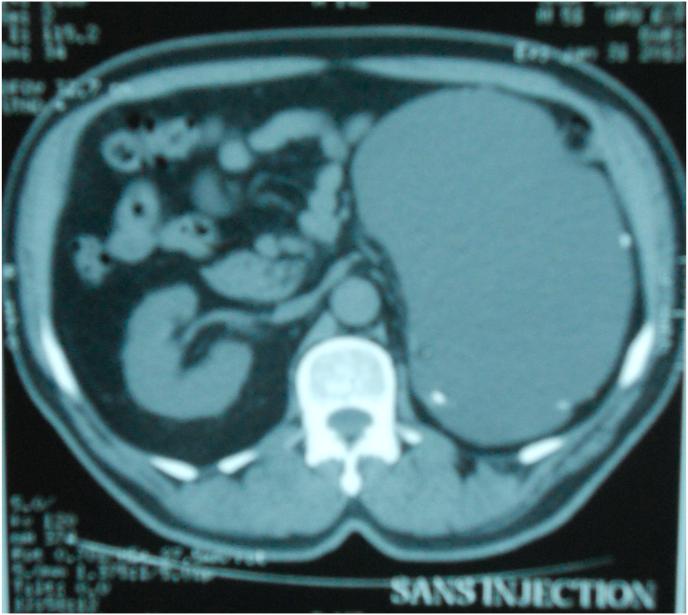

一例巨大肾上腺囊肿病例。

A case of a giant adrenal cyst.

Giant adrenal cysts represent rare clinical entities that are usually discovered incidentally. Here, we describe a patient who presented with nonspecific upper abdominal left pain. Imaging studies revealed a huge left adrenal cyst. Routine laboratory tests and endocrine function tests were all normal. The patient underwent surgery, and the cyst was completely removed with total adrenalectomy. Histological examination revealed a benign epithelial adrenal cyst.The postoperative course was uneventful and the patient had no evidence of recurrence during a 3-year follow-up. We discuss the diagnosis and management of adrenal cysts.

巨大肾上腺囊肿是罕见的临床病症,通常为偶然发现。在此,我们描述一名出现非特异性左上腹疼痛的患者。影像学检查发现一个巨大的左肾上腺囊肿。常规实验室检查和内分泌功能检查均正常。该患者接受了手术,囊肿通过肾上腺全切术被完全切除。组织学检查显示为良性肾上腺上皮囊肿。术后过程顺利,患者在3年随访期间无复发迹象。我们讨论了肾上腺囊肿的诊断和处理。